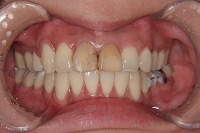

26歳4か月

正面

前歯が出ていて歯並びが悪い事を主訴に来院された、26歳1か月の女性です。診断「歯と歯槽基底の大きさの不調和による叢生」上顎は右側第1小臼歯と左側の犬歯、下顎は抜歯をせず治療を行いました。